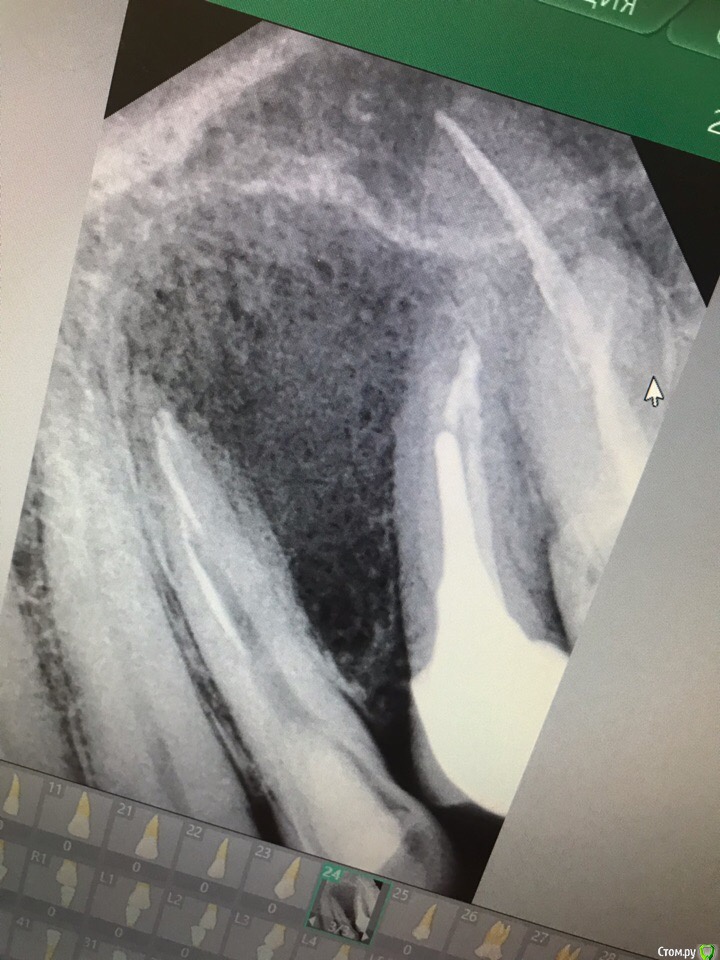

garett Опубликовано 10 августа, 2019 Поделиться Опубликовано 10 августа, 2019 Доброго времени суток! Пишу вот с какой проблемой - не так давно, в начале июня заметил постороннее ощущение между верхним 4 и 5 зубом слева. Было похоже на то, будто что-то застряло между зубами. Вычищал, полоскал - ничего нет в кармане, но ощущение периодически появлялось. Нащупал между этими зубами как бы припухлость. Побежал в местную стоматологию, там сказали, что немного воспалена костная ткань между зубами, сделали рентген и КТ. Да, говорят, почему-то воспален этот участок. Но каналы запломбированы, с зубами проблем не видят. Пятерка - там в 2015 пролечены и запломбированы каналы, стоит коронка, за эти годы никаких проблем не было - жевал все подряд. Четверка - там тоже каналы пролечены и стоит пломба. Сказали, что это не периостит, гноя там нет. Температуры и болевых ощущений тоже нет, но чисто механически раздражает. Даже когда сильно улыбаешься, чувствуешь это постороннее включение между зубами. Пошел опять в клинику, терапевт убрала пломбу на четверке, прошла каналы (хотя все равно утверждает, что каналы в норме). Дошли до конца каналов, стали промывать - острая боль. Да, говорит, там воспаление есть, но каналы сухие, никакого гноя нет. Заложила лекарство, поставила временную пломбу. Первый день после этой манипуляции очень болело это место, даже как будто постреливания такие острые точно у верхушки корня 4 зуба. К вечеру прошло. Но припухлость все равно осталась. Ни хуже, ни лучше. Что это может быть такое? Травм механических не было, очень твердого не жую, как правило. И сейчас жевать вполне можно этими зубами, но ощущение как будто давления между зубами мешает жить. Пугает, что врачи как будто сами не знают, что делать. Терапевт спрашивала, не было ли переохлаждения или простуды - действительно была простуда, как раз в конце мая простудился и получается, вот это воспаление возникло после простуды почему-то. Сегодня был на плановом осмотре - сделали снимок (во вложении) - терапевт разводит руками, говорит, нужно к хирургу все-таки, делать надрез и вычищать там что-то, а потом закладывать какой-то препарат, что-то вроде костной ткани, как я понял. Что это все-таки такое? Ссылка на комментарий

Irouil Опубликовано 10 августа, 2019 Поделиться Опубликовано 10 августа, 2019 Судя по этому снимку есть вероятность, что коронка на "пятерке" давит на десну и вызывала воспалительный процесс. Надо ещё смотреть в полости рта, конечно, и зондировать. Ссылка на комментарий